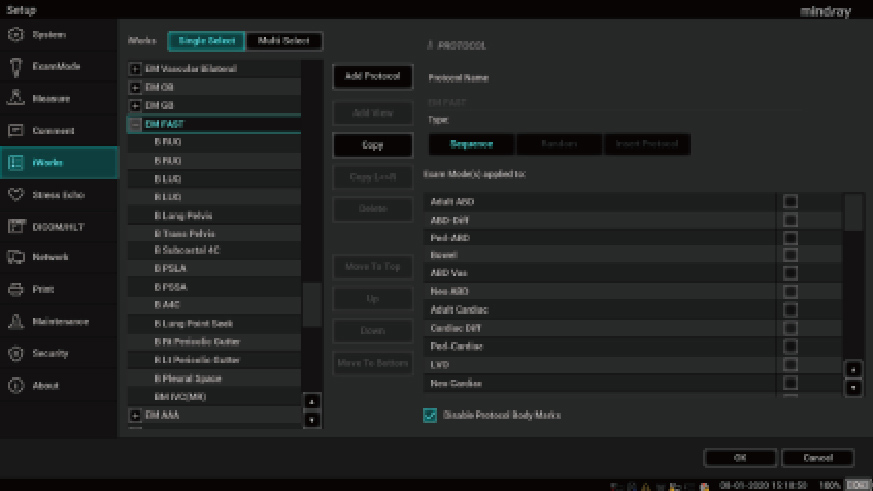

ME-serie

Met een verbeterde beeldkwaliteit op basis van ons revolutionaire ZST+ platform, een spatwaterdicht naadloos bedieningspaneel, een totaal aangepast touchscreen en een speciaal ontworpen workflow, ondersteunt ME artsen voor Kritieke zorg, van de spoedeisende hulp tot anesthesie.

Toepassing voor kritieke zorg

Met uitzonderlijke cardiale beeldvormingsprestaties en geavanceerde analysetools biedt ME een combinatie van kwaliteit, effici?ntie en draagbaarheid voor kritieke zorgscenario's.